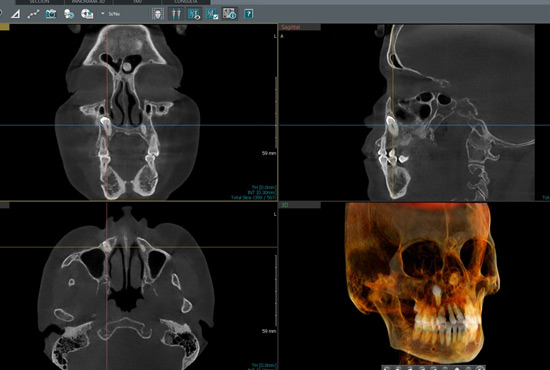

La Tomografía Cone Beam ofrece imágenes 3D detalladas del maxilar y los dientes, permitiendo diagnósticos precisos y una planificación eficaz de tratamientos complejos.

Este software especializado permite analizar y manipular imágenes 3D obtenidas por tomografía Cone Beam. Facilita la planificación quirúrgica y ortodóntica, ofreciendo visualizaciones detalladas desde diferentes ángulos y profundidades.